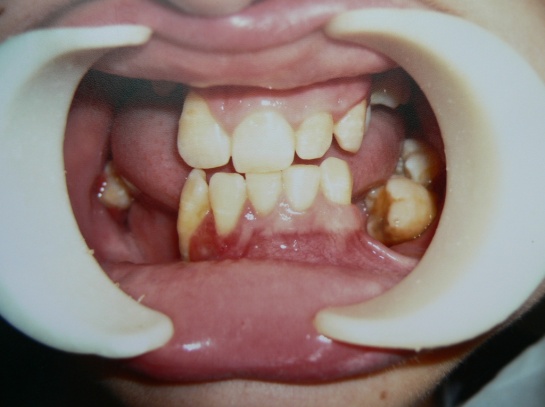

В полости рта выявлено:

- уменьшение величины и формы коронок 12, 24, 25, 44, гипоплазия эмали 34;

- отсутствие 15, 14, 32, 36, 46 зубов;

- конвергенция зубов 13, 35, 43, 42 зубов;

- оголение корней имеющихся зубов на верхней челюсти в боковых отделах;

- отсутствие альвеолярных отростков в боковых отделах нижней челюсти и слева на верхней челюсти;

- пастозность, гиперемия слизистой десны, гипертрофия маргинальной десны и межзубного сосочка в области 32, 43, изъявление десны у 44 зуба;

- глубокие пародонтальные карманы (>6 мм) без отделяемого у 27, 35, 37, 45, 47, патологическая подвижность зубов 3 степени 27, 35, 37, 45, 47 зубов.